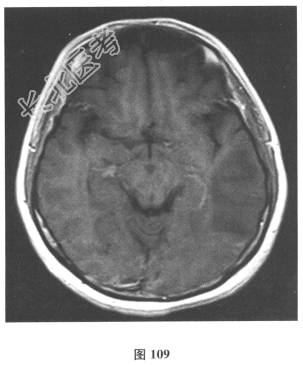

- 简答题2、脑脊液检查:常规、生化均正常,CSF-病毒TORCH(-),抗Hu、Yo、Ri均阴性,OB、MBP正常。血清抗Hu、Yo、Ri均阴性。颅脑MRI显示左颞枕、右顶枕多发长T₁、长T₂信号,Flair高信号,病变累及皮质及皮质下白质,病灶无强化,见图108~图114。)根据颅脑MRI,需要鉴别的疾病应是